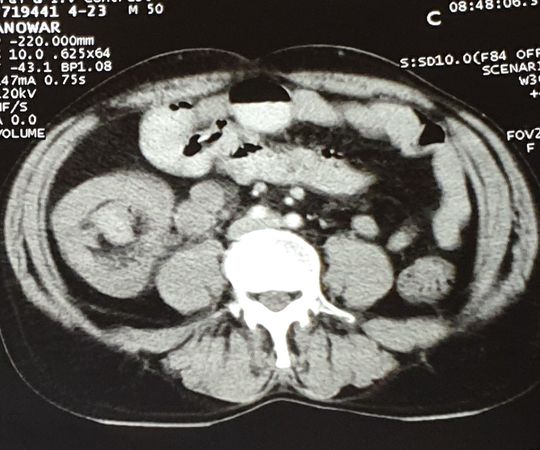

Intussusception

Malignancy

Adult